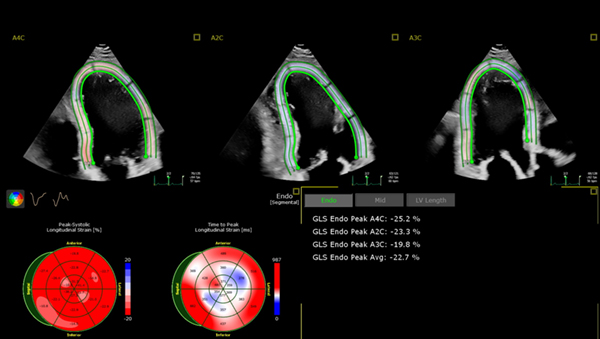

AI技術を活用した自動化機能で検査の効率化

GLS(Global Longitudinal Strain) 解析を行うAutoStrain LVでは,AI技術1により解析に必要な3断面を自動選択する Smart View Selectに対応します。